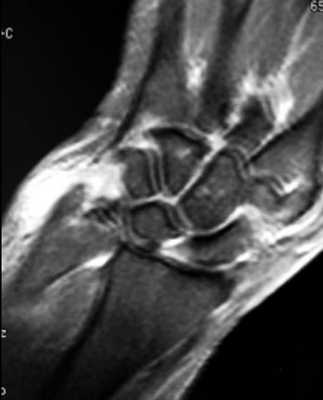

МРТ кисти. Корональная Т1-взвешенная МРТ. Нормальное изображение ладьевидно-полулунной связки. Обозначения: S – ладьевидная кость (scaphoid), L – полулунная кость (lunatum), T- трехгранная кость (triquetrum).

МРТ кисти. Корональная градиентная МРТ. Нормальное изображение полулунно-трехгранной связки. Обозначения: S – ладьевидная кость (scaphoid), L – полулунная кость (lunatum), T- трехгранная кость (triquetrum).

МРТ кисти. Корональная Т1-взвешенная томограмма с подавлением сигнала от жира. Ладьевидно-трапецевидная связка в норме. Обозначения: S- ладьевидная кость, Td – трапециевидная кость, Tm – трапеция.